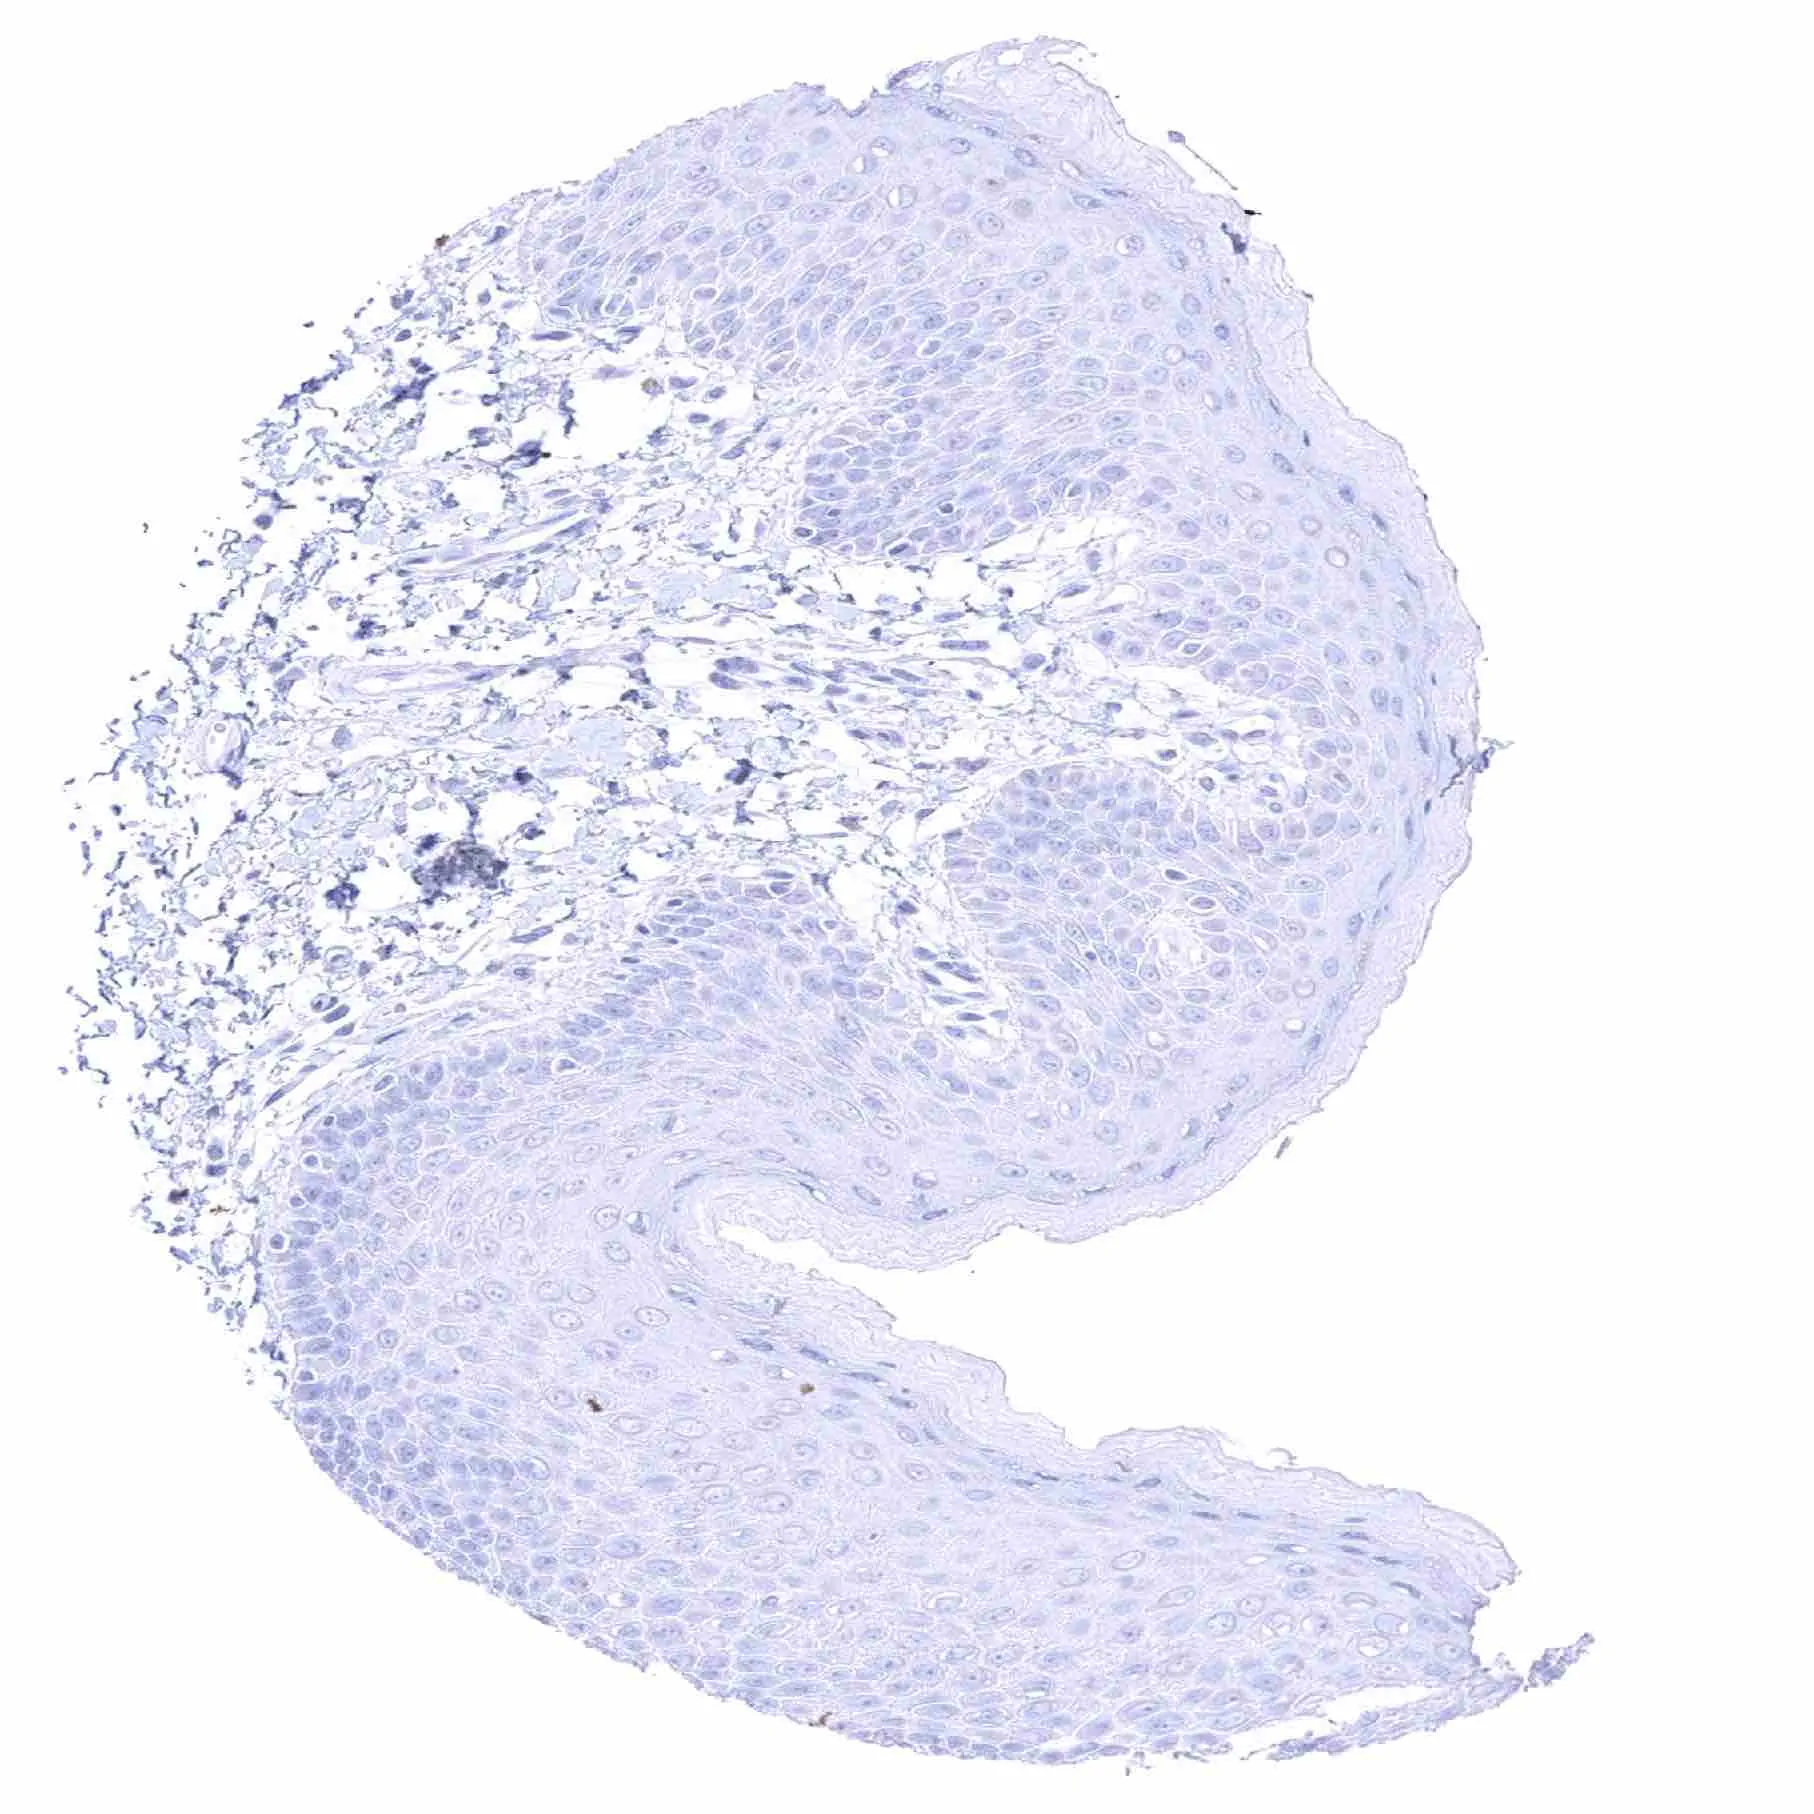

Skin, hairfollicel and sebaceous gland

Skin